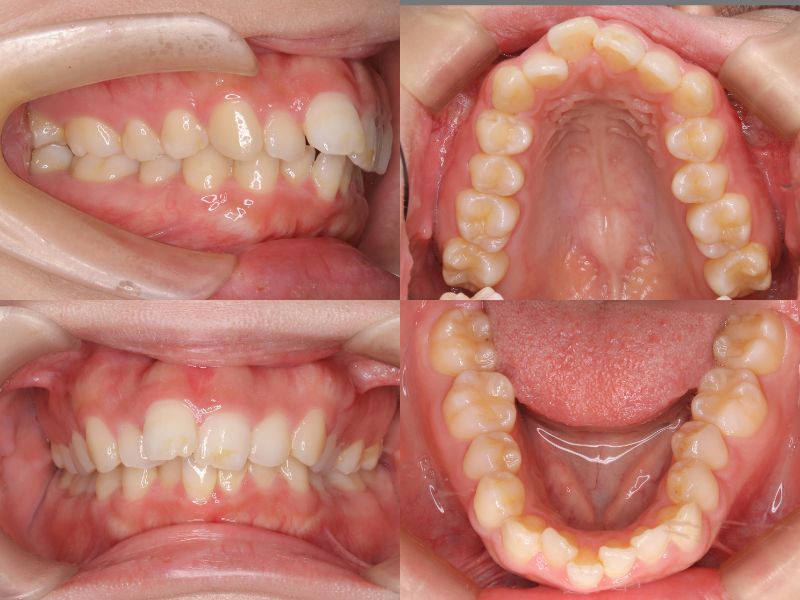

初診時年齢25歳1ヵ月の患者様です。

口元の突出感を主訴にご来院されました。

過蓋咬合と左上7番の根尖性歯周炎が認められたため、通常であれば上下左右4番を抜歯しますが、上下左右5番が処置歯であったため、5番を抜歯しました。

左上7番は再根管治療を行い経過観察としていましたが、治療途中で症状が悪化したため抜歯となりました。

上顎6番を口蓋正中縫合部からアンカースクリューで固定し、さらに上顎2・3間に埋入したアンカースクリューから前歯を圧下しました。